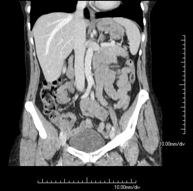

- TC Abdominopélvico Prueba diagnóstica que consiste en obtener imágenes bi y tridimensionales del abdomen y de la pelvis de alta definición anatómica (estructuras óseas, estructuras vasculares, hígado, páncreas, vesícula biliar, riñones, glándulas suprarrenales, bazo, intestino delgado y grueso, vejiga, útero y ovarios, próstata y vesículas seminales, uréteres, etc.) mediante el empleo de un equipo de TC (Tomografía Computarizada). La mayoría de estudios requieren el empleo de contraste yodado. Prueba diagnóstica que consiste en obtener imágenes bi y tridimensionales del abdomen y de la pelvis de alta definición anatómica (estructuras óseas, estructuras vasculares, hígado, páncreas, vesícula biliar, riñones, glándulas suprarrenales, bazo, intestino delgado y grueso, vejiga, útero y ovarios, próstata y vesículas seminales, uréteres, etc.) mediante el empleo de un equipo de TC (Tomografía Computarizada). La mayoría de estudios requieren el empleo de contraste yodado.

- Angio-TC aorta abdominal  Prueba diagnóstica no invasiva que consiste en el estudio de la arteria aorta abdominal obteniendo imágenes de alta definición anatómica mediante el empleo de un equipo de TC (Tomografía Computarizada) y de contraste yodado. La calidad de las imágenes permite realizar reconstrucciones en 2D y 3D gracias a estaciones de trabajo especializadas en el estudio arterial. Está indicado en aquellos pacientes con enfermedad vascular (aterosclerosis), en aneurismas de aorta, en pacientes con dolor abdominal de posible origen vascular, en estudios pre-quirúrgicos de lesiones adyacentes a la aorta abdominal como "mapa" vascular, etc. La información obtenida de forma no invasiva es indispensable para los pacientes que requieren tratamiento percutáneo o quirúrgico. En aquellos pacientes que solo requieren un seguimiento de las lesiones vasculares, esta técnica es la técnica no invasiva de elección junto con la angio-RM. Prueba diagnóstica no invasiva que consiste en el estudio de la arteria aorta abdominal obteniendo imágenes de alta definición anatómica mediante el empleo de un equipo de TC (Tomografía Computarizada) y de contraste yodado. La calidad de las imágenes permite realizar reconstrucciones en 2D y 3D gracias a estaciones de trabajo especializadas en el estudio arterial. Está indicado en aquellos pacientes con enfermedad vascular (aterosclerosis), en aneurismas de aorta, en pacientes con dolor abdominal de posible origen vascular, en estudios pre-quirúrgicos de lesiones adyacentes a la aorta abdominal como "mapa" vascular, etc. La información obtenida de forma no invasiva es indispensable para los pacientes que requieren tratamiento percutáneo o quirúrgico. En aquellos pacientes que solo requieren un seguimiento de las lesiones vasculares, esta técnica es la técnica no invasiva de elección junto con la angio-RM.